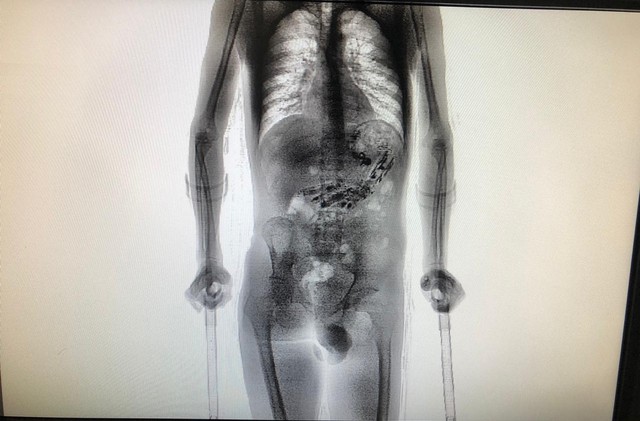

Um detento de 24 anos da Colônia Agrícola Penal de Palhoça, na Grande Florianópolis, precisou passar por cirurgia após retornar de uma saída temporária de sete dias. Ele foi flagrado com 61 objetos dentro do estômago. O caso foi registrado na terça-feira (16).

Ao passar por um scanner de revista corporal, foram encontrados nove celulares e mais 52 objetos como cabo USB, isqueiro, drogas, entre outros.

Os agentes levaram o preso até o Complexo Penitenciário do Estado, em São Pedro de Alcântara, onde realizaram nova inspeção de imagens com o aparelho de scanner e detectaram os objetos metálicos no estômago.